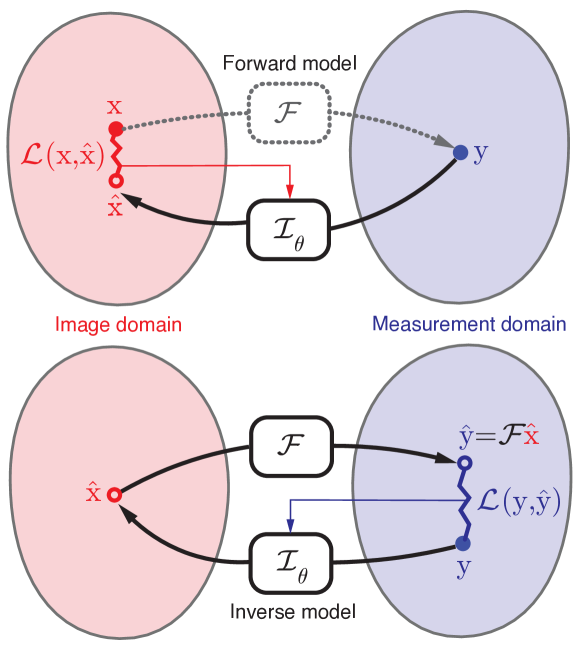

As illustrated in Fig. 1 (top), given an aligned set of samples of latent signals and their corresponding measurements , supervised learning methods aim at estimating the inverse operator that maps the measurements to the corresponding latent signals. We denote by the inverse operator that should invert the action of the forward model. The set of parameters denotes the trainable degrees of freedom – in our case, the weights of the reconstruction neural network. The training is carried out by minimizing the empirical loss

where measures the discrepancy between the estimated latent signal and the groundtruth . Typical choices include the Euclidean and the distances. In practice, for image restoration tasks, the operator is modeled as a convolutional neural network and the objective (3) is minimized using stochastic gradient-based solvers. Once the optimal set of parameters has been learned on the training set, the inverse operator is applied to solve the inverse problem with previously unseen inputs.

Solving the above optimization problem yields , i.e., the latent signal at the intermediate stage, as illustrated in Fig. 1 (bottom). Intuitively, we are searching for an image that is parametrized by that best explains the measurement we have in hand. This approach is referred to as self-supervised because the measurements themselves provide the supervision to solve the inverse problem by exploiting the prior induced by the CNN.